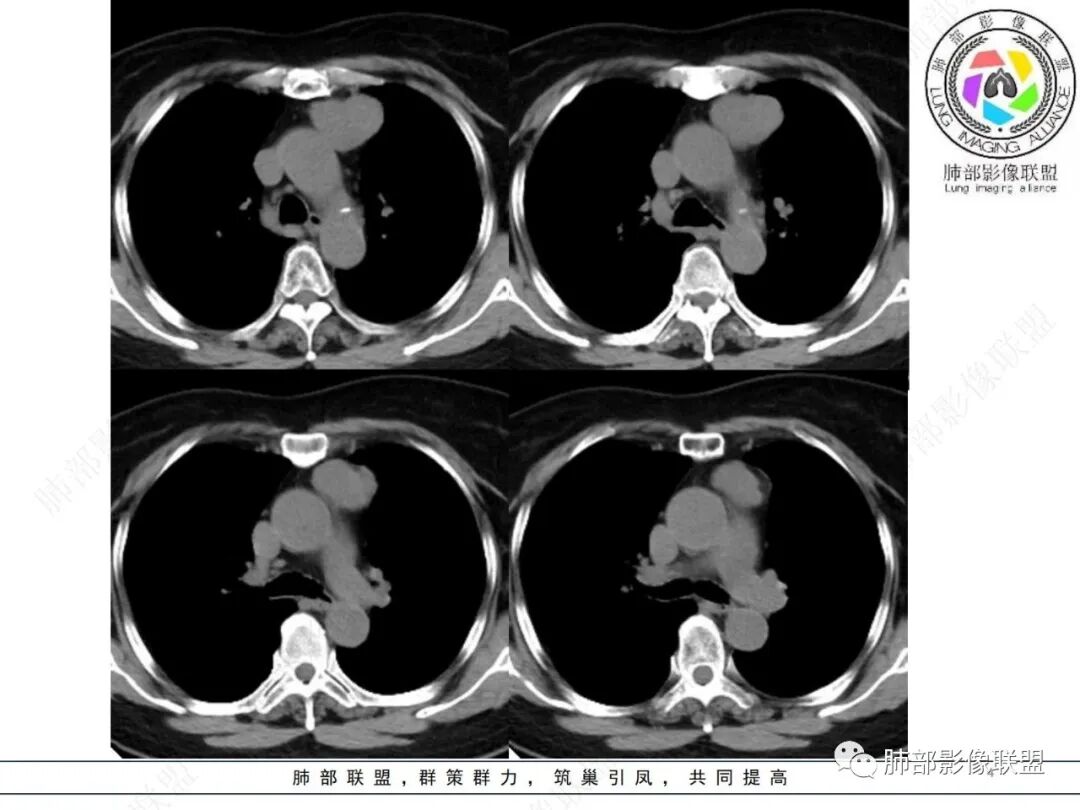

病史,老年女性,检查发现前上纵隔占位。

前上纵隔偏左侧实性病灶,边界清楚,边缘彭隆,浅分叶,内部密度均匀,未见钙化、脂肪密度,周围脂肪间隙清晰。

包膜完整,纤维分隔,结节感明显

平扫密度较均匀,增强渐进性不均匀强化,内见低密度纤维分隔。未见肿大淋巴结。未见胸腔积液。